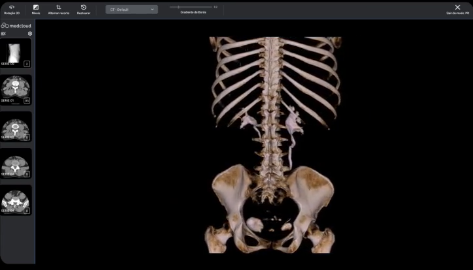

La fusión DICOM PET-CT permite la combinación y sincronización de ambas en una sola imagen o conjunto de datos. Realice análisis más completos superponiendo información metabólica de PET sobre estructuras anatómicas visualizadas por TC para una mejor localización y caracterización de anomalías, como tumores, proporcionando información funcional y estructural en una sola imagen.